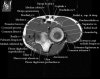

팔꿈치 관절의 MRI 단면 영상

4. MR Arthrography : Useful for evaluation of the collateral ligaments and cartilage surfaces.

5. Elbow Arthrography : UCL pathology in throwers, Osteochondral lesions and repair, Loose bodies